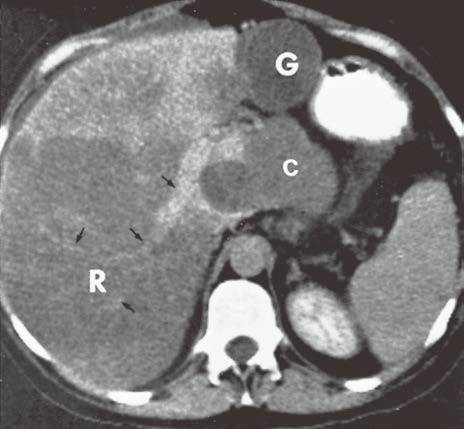

| 脂肪浸润(图1〜图 3) | 肝脏密度弥漫性减低。在肝脏脂肪变的低密度背景下,门静脉表现为高密度结构(平扫时正常门静脉呈低密度)。 | 由于三酰甘油过度沉积所致,见于肝硬化或其他肝脏疾病。正常肝脏平均CT值不低于脾脏,肝脏脂肪 浸润时CT密度较低。肝硬化引起脂肪浸润,伴有肝右叶萎缩,尾状叶体积增大。 |

图1肝硬化患者的肝内脂肪浸润